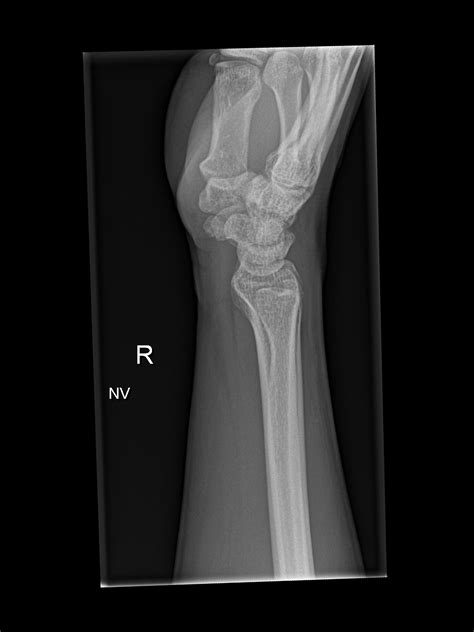

4. Multiple images are taken from different angles to provide a comprehensive view.

Interpreting a Normal Wrist Xray requires a trained eye. Radiologists look for several key features:

• Bone density and structure

• Alignment of the bones

• Presence of fractures or dislocations

• Signs of arthritis or other joint disorders

• Soft tissue abnormalities